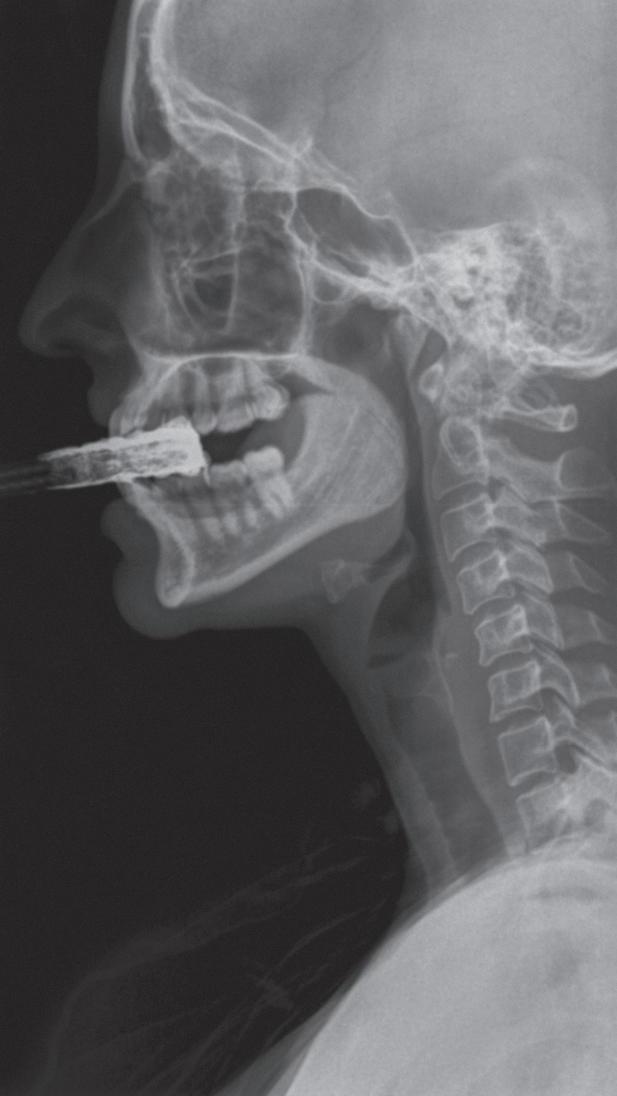

Fig. 1-3. Demonstração das fases da deglutição em visão lateral nas imagens de videofluoroscopia. (a) Fase preparatória oral: incisão dos dentes na bolacha com a raiz de língua elevada, véu palatino abaixado e via aérea aberta; (b) fase preparatória oral: bolo alimentar na porção central da língua com a raiz de língua elevada, véu palatino abaixado e via aérea aberta; (c) fase oral: ejeção do bolo para a região da orofaringe com o movimento anteroposterior de língua e via aérea aberta; (d) fase faríngea: fechamento do véu palatino, elevação da laringe e do osso hioide, PPF = parede posterior de faringe.

Sugere-se que o início da fase faríngea ocorre quando a extremidade inicial do bolo alimentar ultrapassa os pilares anteriores das fauces ou quando a extremidade inicial do bolo transita por qualquer ponto entre os pilares anteriores das fauces e o ponto em que a base da língua cruza com a parte posterior do ramo da mandíbula.4

Segundo a revisão sistemática, autores concluíram que o início da fase faríngea da deglutição foi observado com maior frequência quando a cabeça do bolo estava até a região posterior do ramo da mandíbula ou nas valéculas epiglóticas ao momento do primeiro sinal de excursão do osso hioide.13 Houve grande frequência do início da fase faríngea em valéculas epiglóticas, tanto na população assintomática como na sintomática.

Em seguida a laringe é elevada e anteriorizada por meio do movimento anterossuperior ocorrendo o fechamento no nível das pregas vocais, seguido das pregas vestibulares e da cartilagem epiglótica em contato com as cartilagens aritenoides completando o fechamento vestibular (Fig. 1-3).15,16

Neste momento o bolo alimentar passa pelos recessos piriformes para alcançar o esfíncter esofágico superior (EES), (músculo cricofaríngeo).7 Logo após, inicia-se a fase esofágica pelo relaxamento do EES permitindo a passagem do bolo alimentar em direção ao estômago.7 Lembrando que a tração anterossuperior do complexo hioide-laringe determina a abertura do EES (Fig. 1-6).